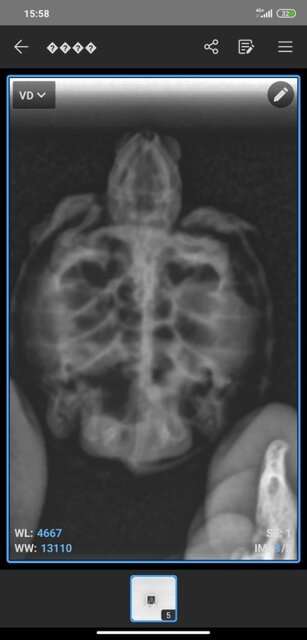

1760179420857.jpg

1760179420854.jpg

1760179420850.jpg

1760179420844.jpg

1760179381867.jpg